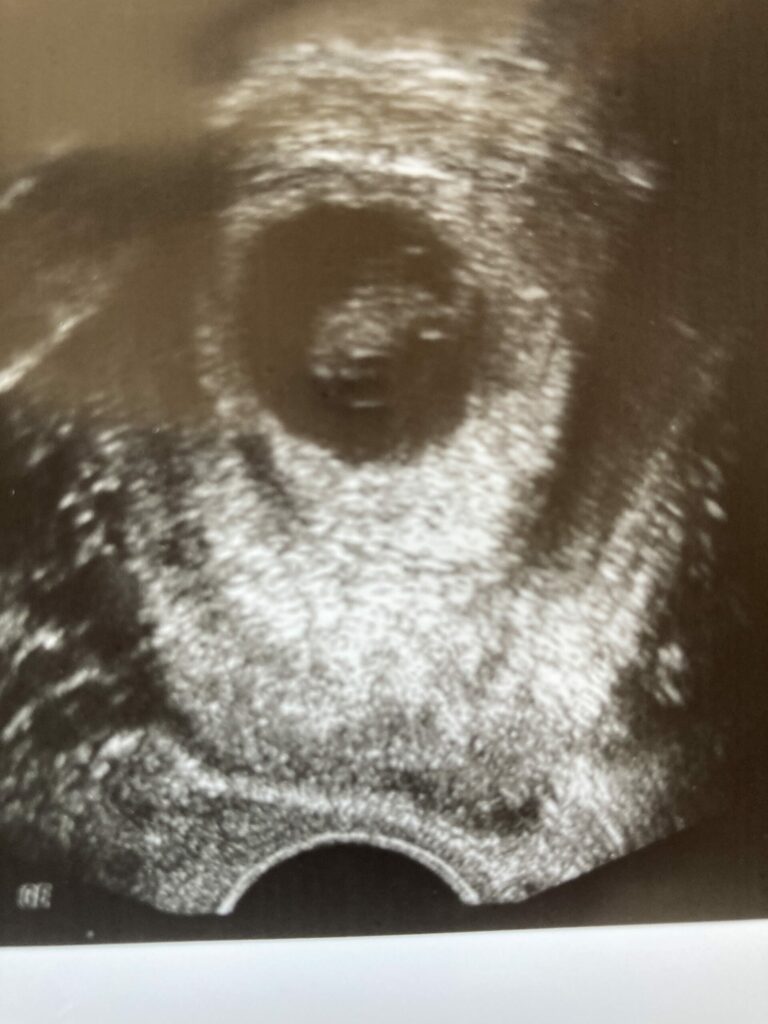

Hallo an das gesamte Team! Was hätten wir nur ohne Sie gemacht? Nach langem Kinderwunsch und einem steinigen Weg sind wir nun schon in der 11 Woche schwanger. Wir sagen danke danke danke, danke, dass Sie nie aufgegeben haben – auch wenn wir kurz davor waren. Wir kommen Sie auf jeden Fall besuchen.